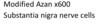

c. after chemotaxis

Azan stain of nerve ganglion